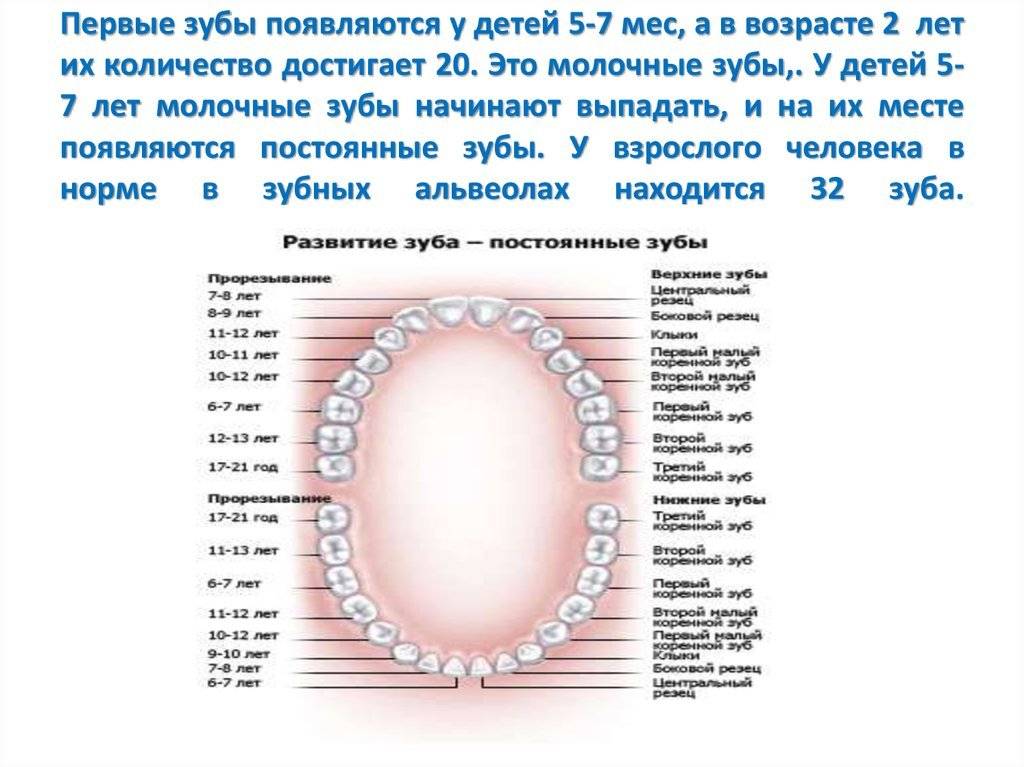

В каком возрасте выпадают молочные зубы у детей?

Во сколько лет выпадают молочные зубы у детей? Смена молочных на коренные начинается в среднем с 5-6 лет, но процесс, предшествующий выпадению происходит еще задолго до этого. Начиная с 4-6 лет, у ребенка рядом с молочными зубами прорезываются третьи моляры (самые дальние в зубном ряде, так называемые «шестерки»), которые являются первыми постоянными зубками.

Выпадают они в течение 5-8 лет, начиная с 5-летнего возраста и до достижения ребенком 13 лет. К 14 годам зубной ряд подростка должен состоять из всех коренных зубов.

При этом процесс, сроки и порядок выпадения будет зависеть от того, в какой последовательности и когда прорезались зубки у младенца. Чем позже появились первые зубы, тем дольше не будет происходить их смена на постоянные. Прорезываются коренные зубы симметрично с двух сторон. У девочек этот процесс начинается раньше, у мальчиков – немного позже.

В большинстве случаев зубы, находящиеся снизу, выпадают раньше, чем соответствующие им резцы, клыки или моляры, находящиеся в верхней челюсти.

Когда выпадают молочные зубы у детей

Процесс смены достаточно длительный. Знание сроков помогает родителям определить причину появления болей и отека десны. Начинается этот период примерно к 6-7 годам. Продолжается смена 6-7 лет и завершается к 12 годам. Сколько именно займет период, зависит от индивидуальных особенностей ребенка и его здоровья. Примечательно, что у девочек временные зубы выпадают быстрее, чем у мальчиков.